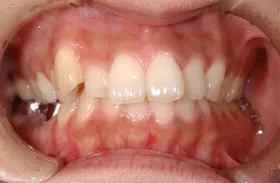

生まれつき歯が生えてこなかったケース

■治療前:生まれつき下顎左右前歯がなく隙間がある

■治療後:矯正治療後、下顎左右3番の2本にインプラント治療

| 主訴 | 生まれつき歯がなく隙間があり、審美障害・咀嚼機能障害がある |

|---|---|

| 治療方法 | インプラント治療 + 矯正治療 |

| 治療期間 | インプラント治療 約6ヶ月 |

| 通院回数等 | インプラント治療 約6回 |

| 費用 | 約94万円(税込) |

| リスク・副作用 | 術後の腫れ・痛み |